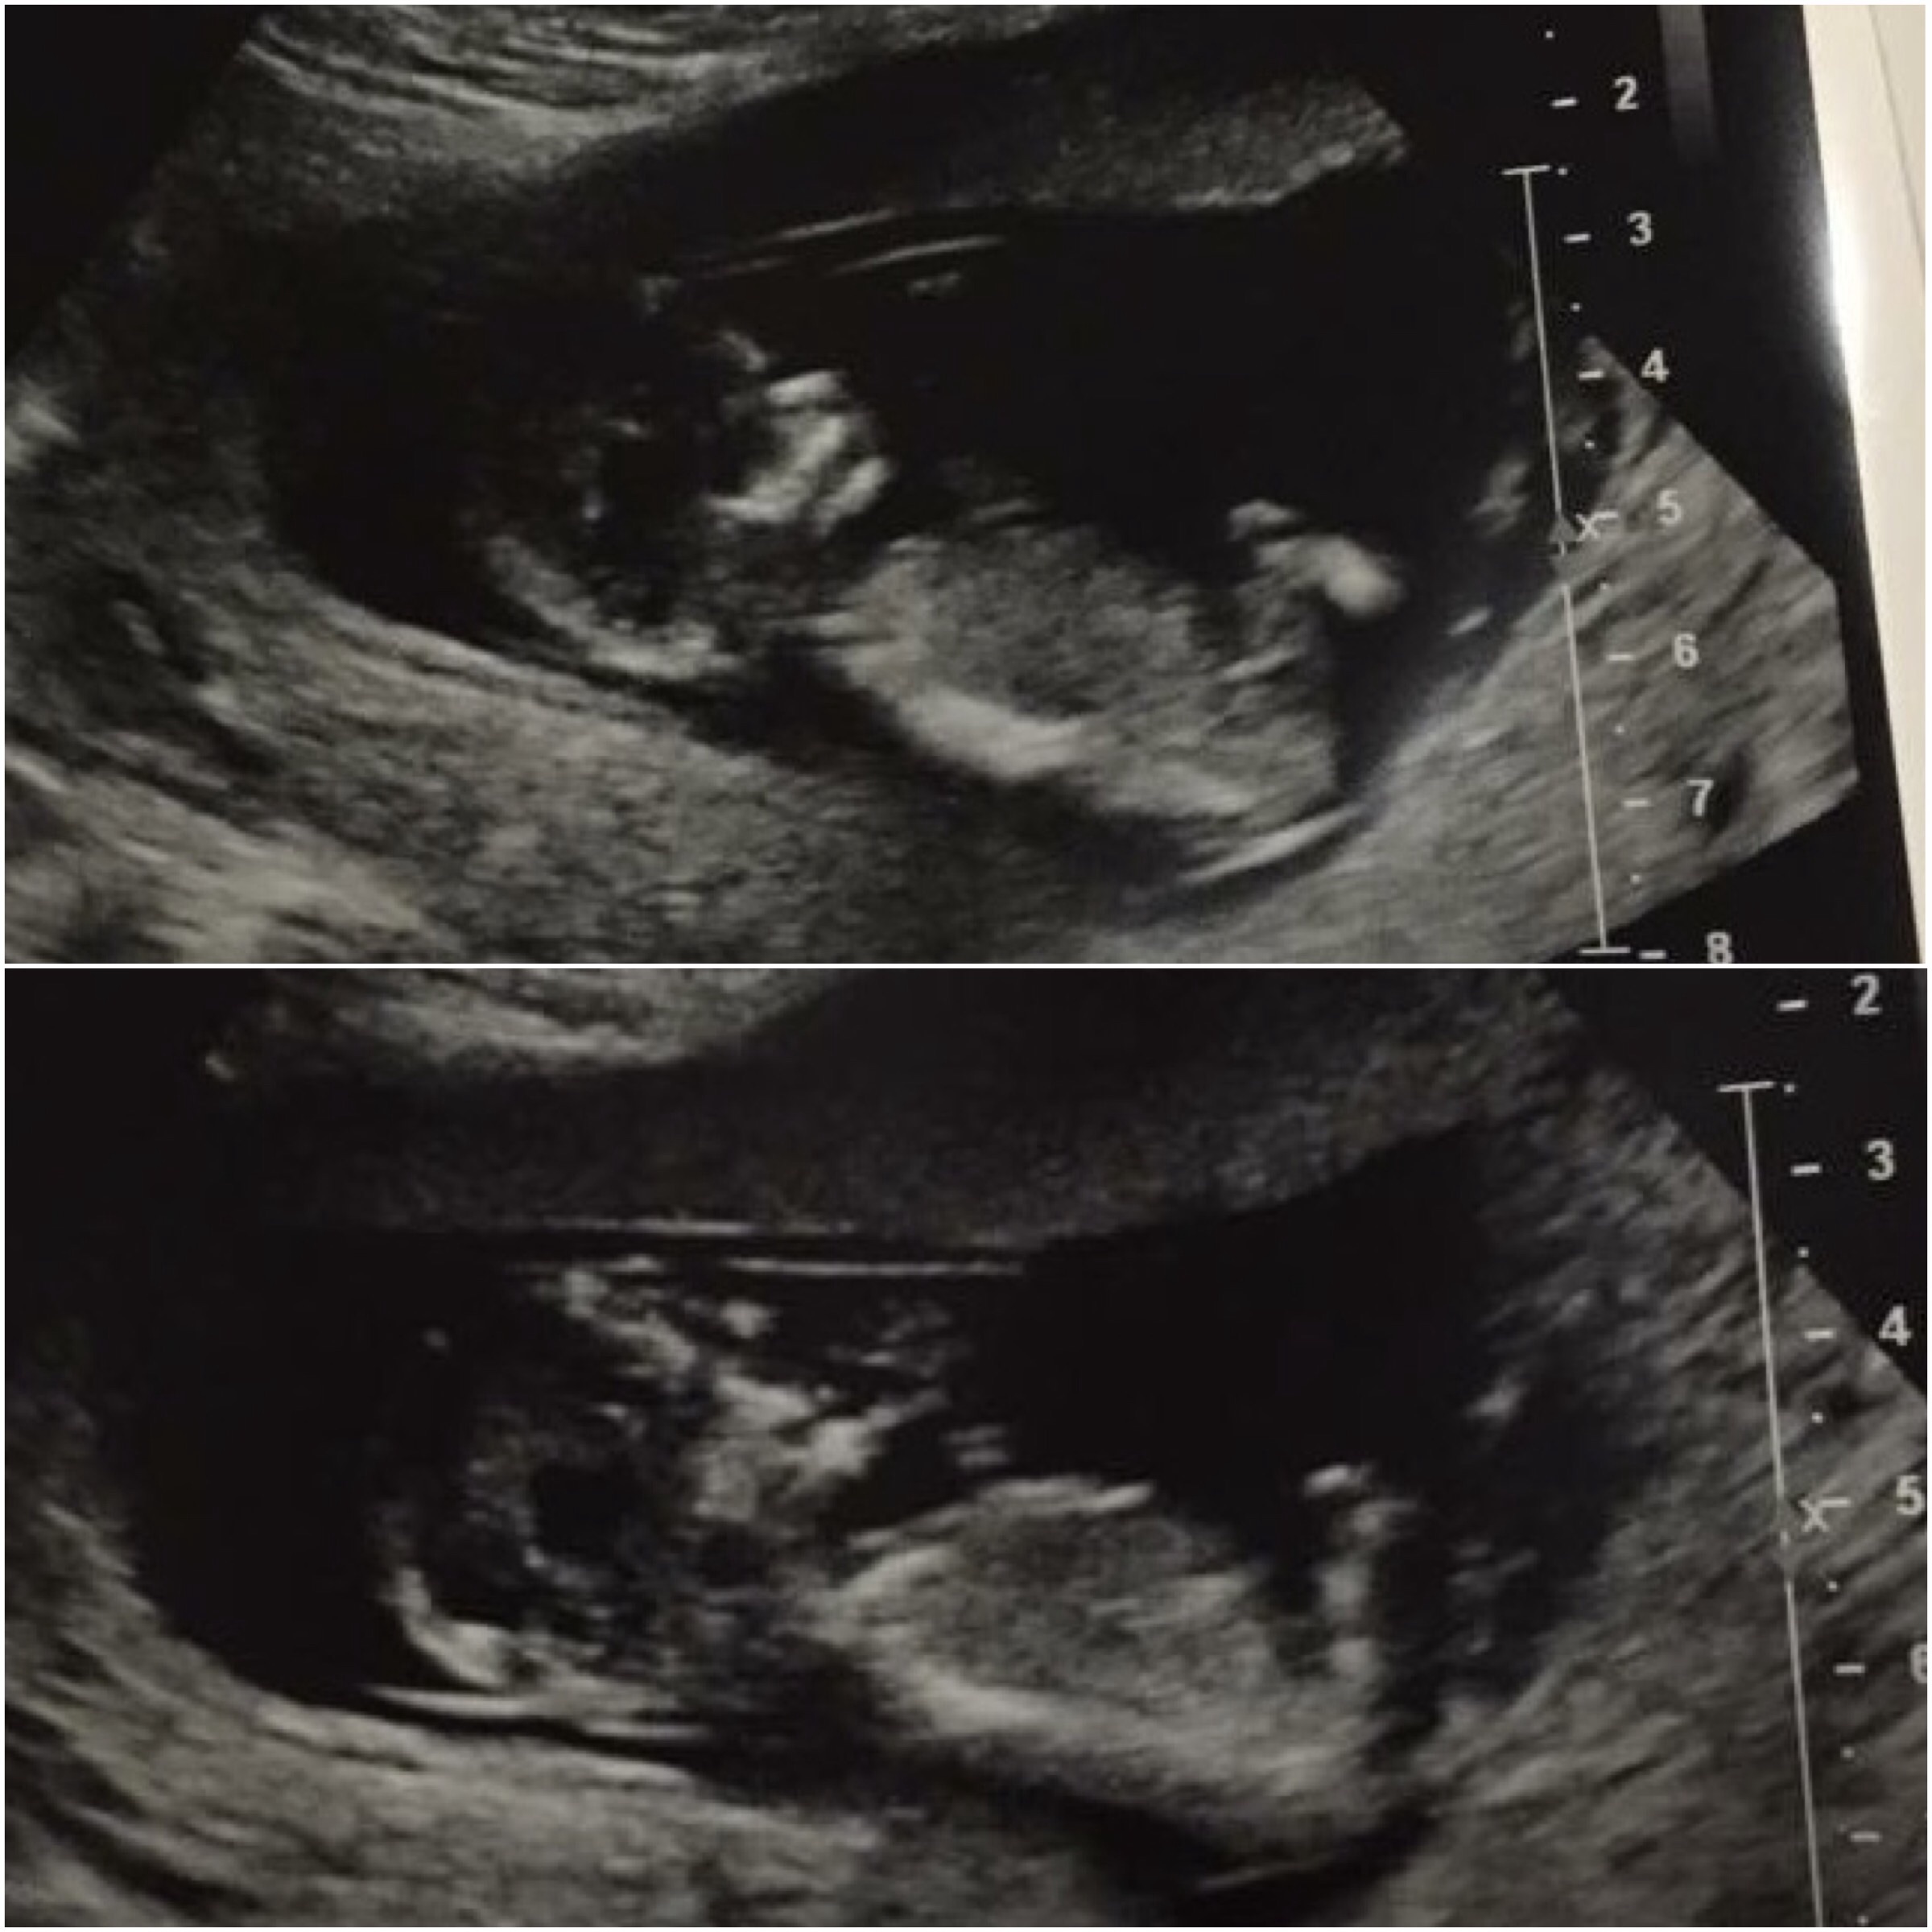

Any nub? I think the line on the top photo is in the wrong spot to be a nub?

I think I can see something forked on the bottom picture?

Baby is 13+ 0Attachment 24660

Leaning boy based on angle on first pic, but it could also be girl, the nub is long and forked. Sorry I can't give a good answer!

Giving a boy lean - not very good images for guessing sorry. What I think I can see is angled.

Leaning boy. I am having a hard time deciding how curled up baby is;)

Sorry I don't see a nub.

its got very bad motion blur so no telling on this one really.